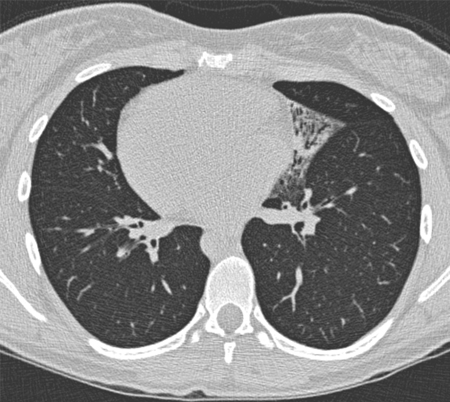

Tomografia computadorizada do tórax com vias aéreas dilatadas e espessadas e um padrão de árvore em brotamento

Dos arquivos do Dr. Sangeeta M. Bhorade; uso autorizado